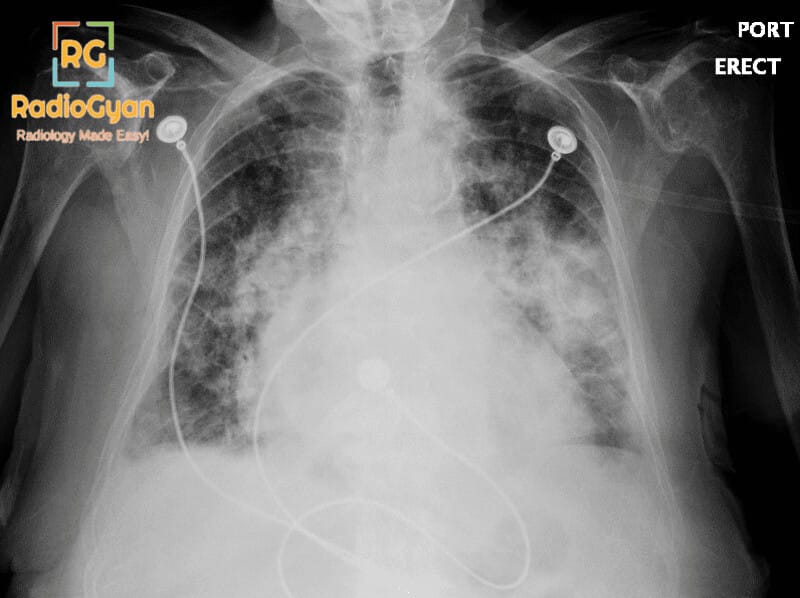

The bat-wing appearance represents bilateral symmetrical perihilar opacities that typically indicate accumulation of fluid or cellular material in the alveoli and interstitium of the lungs. The most common cause is pulmonary edema from cardiac sources such as heart failure, characterized by fluid accumulation due to elevated pulmonary venous pressure and increased hydrostatic pressure in the pulmonary capillaries. However, this sign is not exclusive to cardiac causes and can also be seen in pneumonia, pulmonary hemorrhage, inhalation injuries, sarcoidosis, bronchoalveolar carcinoma, and pulmonary alveolar proteinosis. The appearance typically demonstrates a ground-glass pattern and characteristically spares the lung cortices, preserving the peripheral lung zones while concentrating in the central perihilar regions. The sign is symmetrical and may be associated with cardiomegaly when the underlying cause is cardiac in nature. Air bronchograms may be visible, representing patent airways surrounded by consolidated or edematous lung tissue.

The sign is named “bat-wing appearance” because the bilateral symmetrical perihilar opacities that radiate outward from the hilum resemble the wings of a bat in extension, creating a characteristic butterfly or wing-like silhouette on frontal radiographic views. The symmetrical distribution and shape mimicking a bat’s outstretched wings provide an intuitive visual descriptor for this radiological pattern.

The bat-wing appearance develops through the accumulation of fluid in the pulmonary alveoli and interstitial spaces. In cardiac pulmonary edema, elevated left atrial pressure (from left ventricular dysfunction, mitral valve disease, or fluid overload) increases hydrostatic pressure in the pulmonary capillaries, forcing fluid across the capillary membrane into the interstitium and alveolar spaces. This fluid-filled tissue appears opaque on radiographs. The perihilar concentration occurs because pulmonary venous pressure is highest centrally at the hilum and decreases peripherally. As edema progresses, it advances from the perihilar regions toward the periphery. The bilateral symmetry reflects the uniform distribution of pulmonary venous pressure elevation across both lungs. In non-cardiac causes such as pneumonia or alveolar proteinosis, similar central consolidation patterns develop through different mechanismsโeither inflammatory cellular infiltration or protein depositionโbut produce the same radiographic appearance.